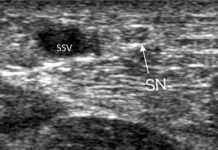

But what happens when you face Dual-Channel Reflux—where both the Great Saphenous Vein (GSV) and the Anterior Accessory Saphenous Vein (AASV) are failing together?

AASV: A Fragile Target for Heat

The AASV is notoriously difficult for thermal ablation. It sits very close to the skin and often follows a zig-zag path.